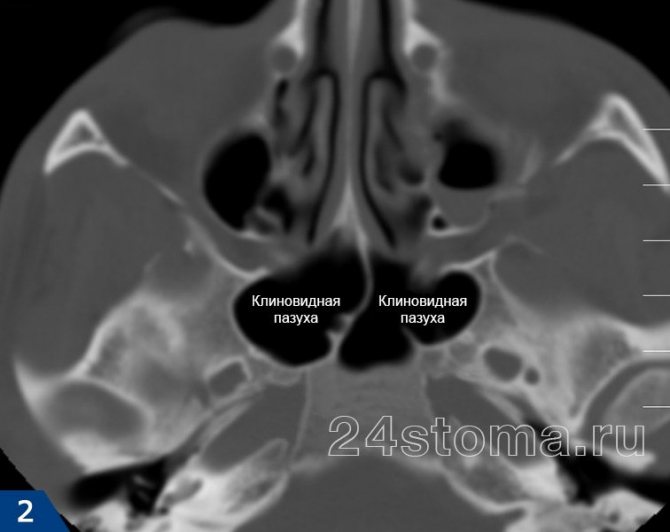

Сфеноидит – это воспаление клиновидных пазух, которые являются одними из четырех пар придаточных пазух носа. Изолированный сфеноидит встречается крайне редко (в 1-2% от всех случаев острых и хронических синуситов). Чаще всего сфеноидит возникает как следствие воспаления в расположенных рядом решетчатых пазухах, которое носит название «этмоидит».

Что такое клиновидная пазуха?

Клиновидная пазуха – это полость в толще клиновидной кости, которая располагается достаточно глубоко, практически в центре головы, на границе мозговой, лицевой частей черепа и основания мозга.

Эту кость еще называют основной. Вблизи нее локализуются очень важные структуры: непосредственно над клиновидным синусом находится гипофиз, с латеральной стороны к ней примыкает пещеристый синус, в котором проходят внутренняя сонная артерия и некоторые ветви черепных нервов. Сзади находятся отделы основания мозга.

Дно клиновидного синуса образует крышу носоглотки. Существует две клиновидные пазухи, каждая из них имеет сообщение с полостью носа.